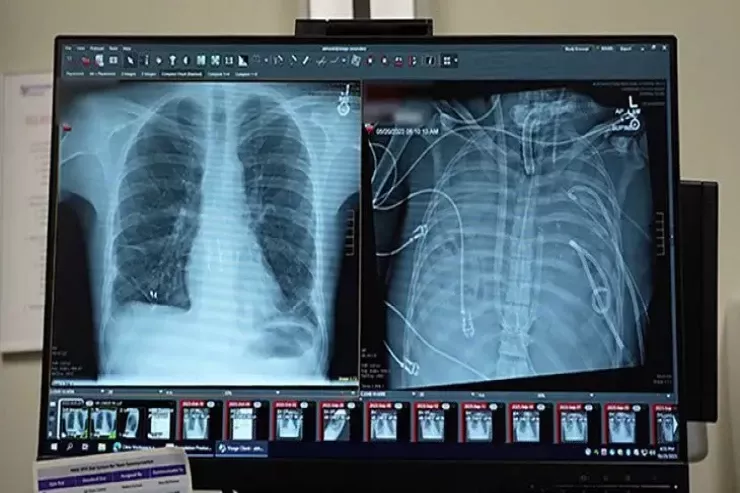

ABŞ-ın klinikalarından birində elmi-fantastik hadisə baş verib.  Bir qrup cərrah pasiyentin ağciyərləri tamamilə çıxarıldıqdan sonra onu iki sutka ərzində həyatda saxlamağa nail olublar. Bu kritik zaman aralığı donor orqanların uğurlu transplantasiyasına aparan körpü rolunu oynayıb. B

Lent.az xarici mediaya istinadən xəbər verir ki, həmin pasiyent hələ də yaşayır və iki il keçməsinə baxmayaraq, ağciyərləri tam funksional şəkildə işləyir.

Pasiyent 2023-cü ildə mövsümi qrip keçirən 33 yaşlı kişidir. Xəstəlik qısa müddətdə ağır tənəffüs çatışmazlığına çevrilib və ikitərəfli pnevmoniya, sepsis və kəskin respirator distres sindromu ilə ağırlaşıb.

Ağciyərləri bürüyən infeksiya müalicəyə tabe olmayıb və tənəffüs orqanları bütün orqanizmi zəhərləyən ölümcül ocağa çevrilib. Həkimlər çıxılmaz bir dilemma ilə üz-üzə qalıblar. Ağciyərlər çıxarılmasa ölüm qaçılmaz olub, lakin onların tam çıxarılması da hökm kimi görünüb, çünki insan ağciyərsiz yaşaya bilməz.

Xilasın açarı ABŞ-ın Şimal-Qərb Universitetinin mütəxəssisləri tərəfindən hazırlanan, TAL kimi tanınan tam süni ağciyər sistemi olub. Bu  texnologiya qaz mübadiləsi funksiyasını öz üzərinə götürərək qanın oksigenlə zənginləşdirilməsini və karbon qazının xaric edilməsini təmin edib, eyni zamanda qan dövranını tənzimləyərək ürəyin üzərindəki ölümcül yükü azaldıb.

Məhz bu sistem cərrahlara hər iki zədələnmiş ağciyəri radikal şəkildə çıxarmağa və uyğun donor orqan tapmaq üçün saatlar qazanmağa imkan verən süni boşluq rolunu oynayıb.

48 saat ərzində pasiyent əvvəllər həyat üçün mümkünsüz sayılan bir vəziyyətdə olub. Onun qanı bədən xaricində oksigenlə zənginləşdirilib, həkimlər isə gələcəyi uğrunda mübarizə aparıb.